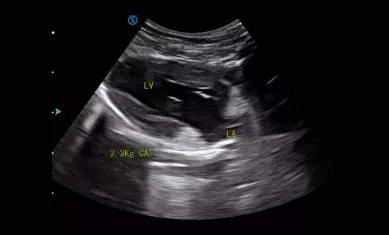

VP2 provides various applications for veterinary diagnosis with micro convex probe and linear probe.

Heart